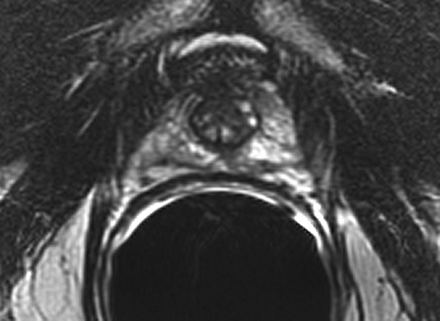

Sextant biopsies were taken routinely ≈ 1 cm apart in the parasaggital plane bilaterally, at the base, mid-gland and apical regions of the prostate, as described by Hodge et al. [1]. In addition, six further biopsies were obtained, two from the TZ and four from the lateral PZ, as depicted in Fig. 1. The TZ biopsies were taken at the level of the mid-gland where the TZ was most prominent. The lateral PZ biopsies were taken by positioning the probe just medial to the lateral edge of the prostate at the base and mid-gland regions bilaterally, as described by Chang et al. [8]. This method generally allowed any area of DRE abnormality or suspicious hypoechoic lesion noted on TRUS to be incorporated into the biopsy protocol. All patients underwent the same biopsy strategy with no variance for gland size. Biopsies were obtained using an 18 G core-biopsy needle mounted on a spring-loaded automatic biopsy gun. All patients were placed in the left lateral decubitus ('knee-chest') position and all were examined with no prior bowel preparation. The procedure was generally well tolerated and no patient required intravenous sedation or narcotic analgesia. All TRUS was undertaken by the same operators (D.R.G. and N.S.), either personally, or when supervising a higher urological trainee.